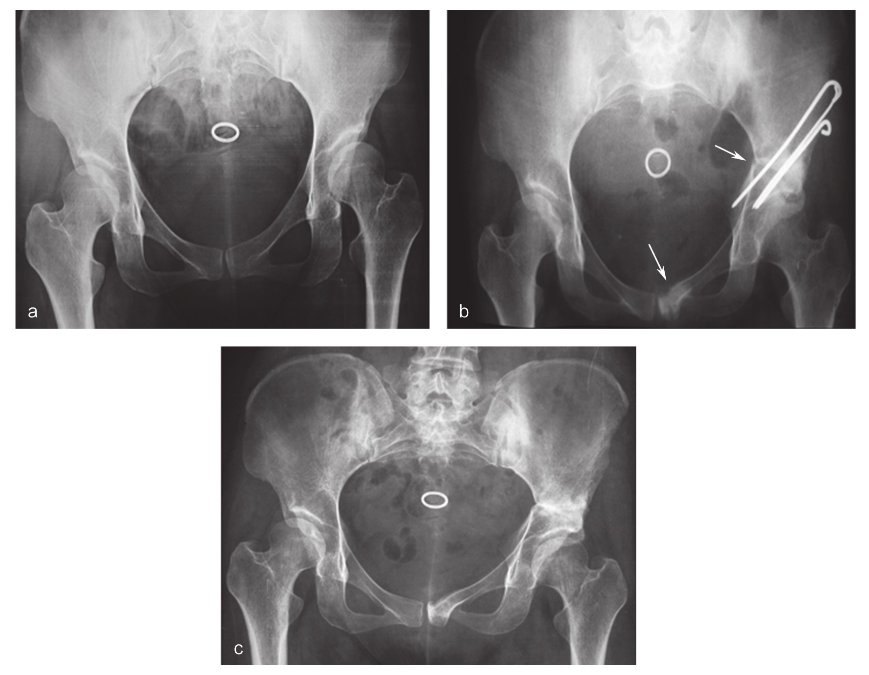

图2 截骨位置不佳的骨盆正位X线片,箭头所示截骨位置过于远离耻骨联合而靠近闭孔,破坏了闭孔的完整性。

基本处理与Salter骨盆单一截骨术相同,髋人字形石膏固定髋关节于外展30°、屈曲与内旋各15°位。也可患肢持续皮牵引,牵引重量2kg,主要目的是限制髋关节屈曲活动以保护缝匠肌和股直肌在骨盆附着处的正常愈合。相较于单一截骨术,石膏固定时间建议延迟至6~8周,之后主动练习髋关节屈伸活动:鼓励患者坐起,双手交叉触脚,练习穿袜子。可辅以CPM机被动锻炼,分别于术后1个月、2个月、3个月、6个月、9个月复查X线片,根据截骨处愈合情况决定负重和去除内固定的时间。负重时间相较于单一截骨术适当延后(图4)。

图4 Sutherland双联截骨术患者随访情况。a.患者女性,28岁。主因“双髋疼痛、跛行”入院。X线片示双髋DDH;b.Sutherland双联截骨术后,箭头所示截骨位置;c.去除牵引后患者拄双拐开始下床,患肢不负重,术后2个月,逐渐开始增加患肢负重及加强肌肉力量的训练,术后3个月弃拐行走,截骨愈合后取出内固定,术后左髋疼痛缓解,X线片示左股骨头覆盖率明显增加。